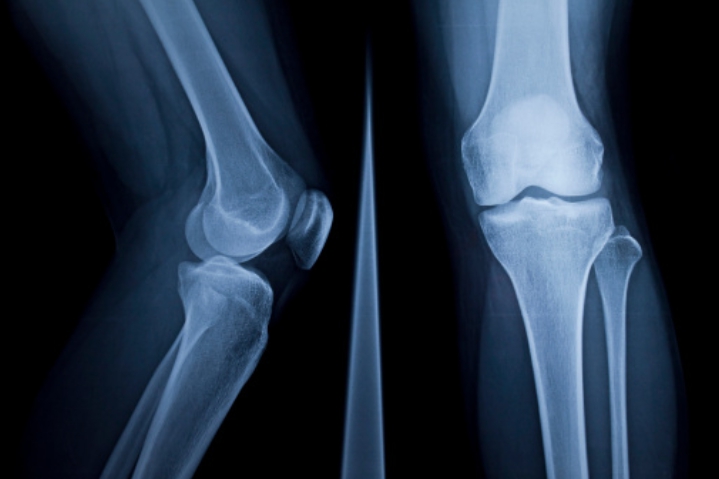

연골이 마모되면 뼈와 뼈 사이가 좁아져 관절염이 발생하여 통증이 생깁니다. 이때 콘드로이친을 복용하면 관절염 개선에 도움이 됩니다.

콘드로이친은 마모되어 얇고 연약해진 연골의 내마모성과 볼륨 유지를 개선하여주는 역할을 합니다. 연골을 보호하고 염증이 생긴 관절에 쿠션을 제공하여 통증을 완화시키고 일상생활을 원활하게 하도록 하는데 도움이 됩니다.